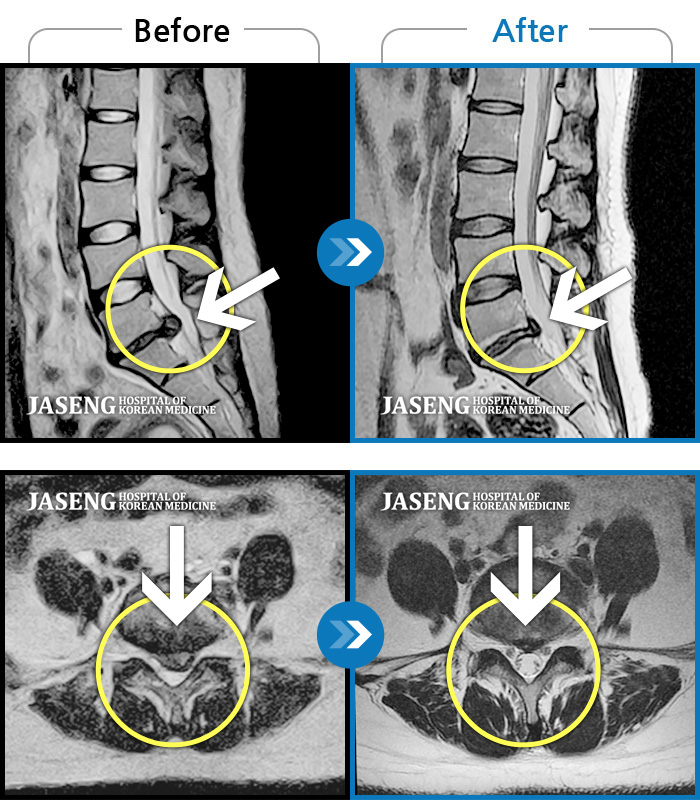

Before

After

환자에게 사전 동의를 받아 동일 조건에서 촬영되었습니다.

개인에 따라 치료 후 부작용이 발생할 수 있으니 의료진과 상담 후 치료를 진행하시기 바랍니다.

심한 허리 통증과 우측 다리 통증

통증으로 거동 불편